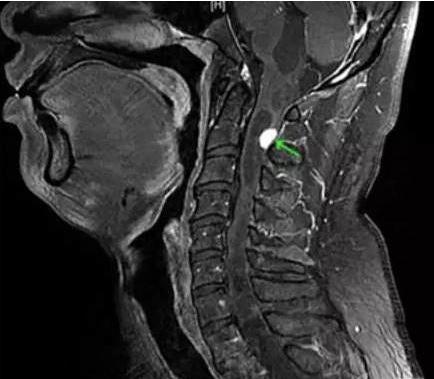

Un homme de 35 ans souffrant d'un hoquet persistant depuis plus de deux jours était si insupportable qu'il s'est rendu deux fois à l'hôpital avant et après et n'a reçu qu'un simple traitement symptomatique.

Ce n'est qu'à sa troisième visite que les médecins ont découvert une tumeur se développant à l'arrière de son cou et appuyant sur son nerf phrénique.Et le rôle de ce nerf est de transmettre des impulsions du cerveau au diaphragme pour compléter le mouvement respiratoire。

Ainsi, lorsque le nerf phrénique de cet homme a été comprimé, il a envoyé tous les mauvais signaux au diaphragme.Provoque une contraction involontaire du diaphragme.Cela provoque des rots constants chez le patient.